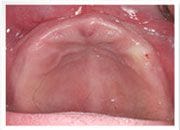

林小姐求診時, 上顎無牙